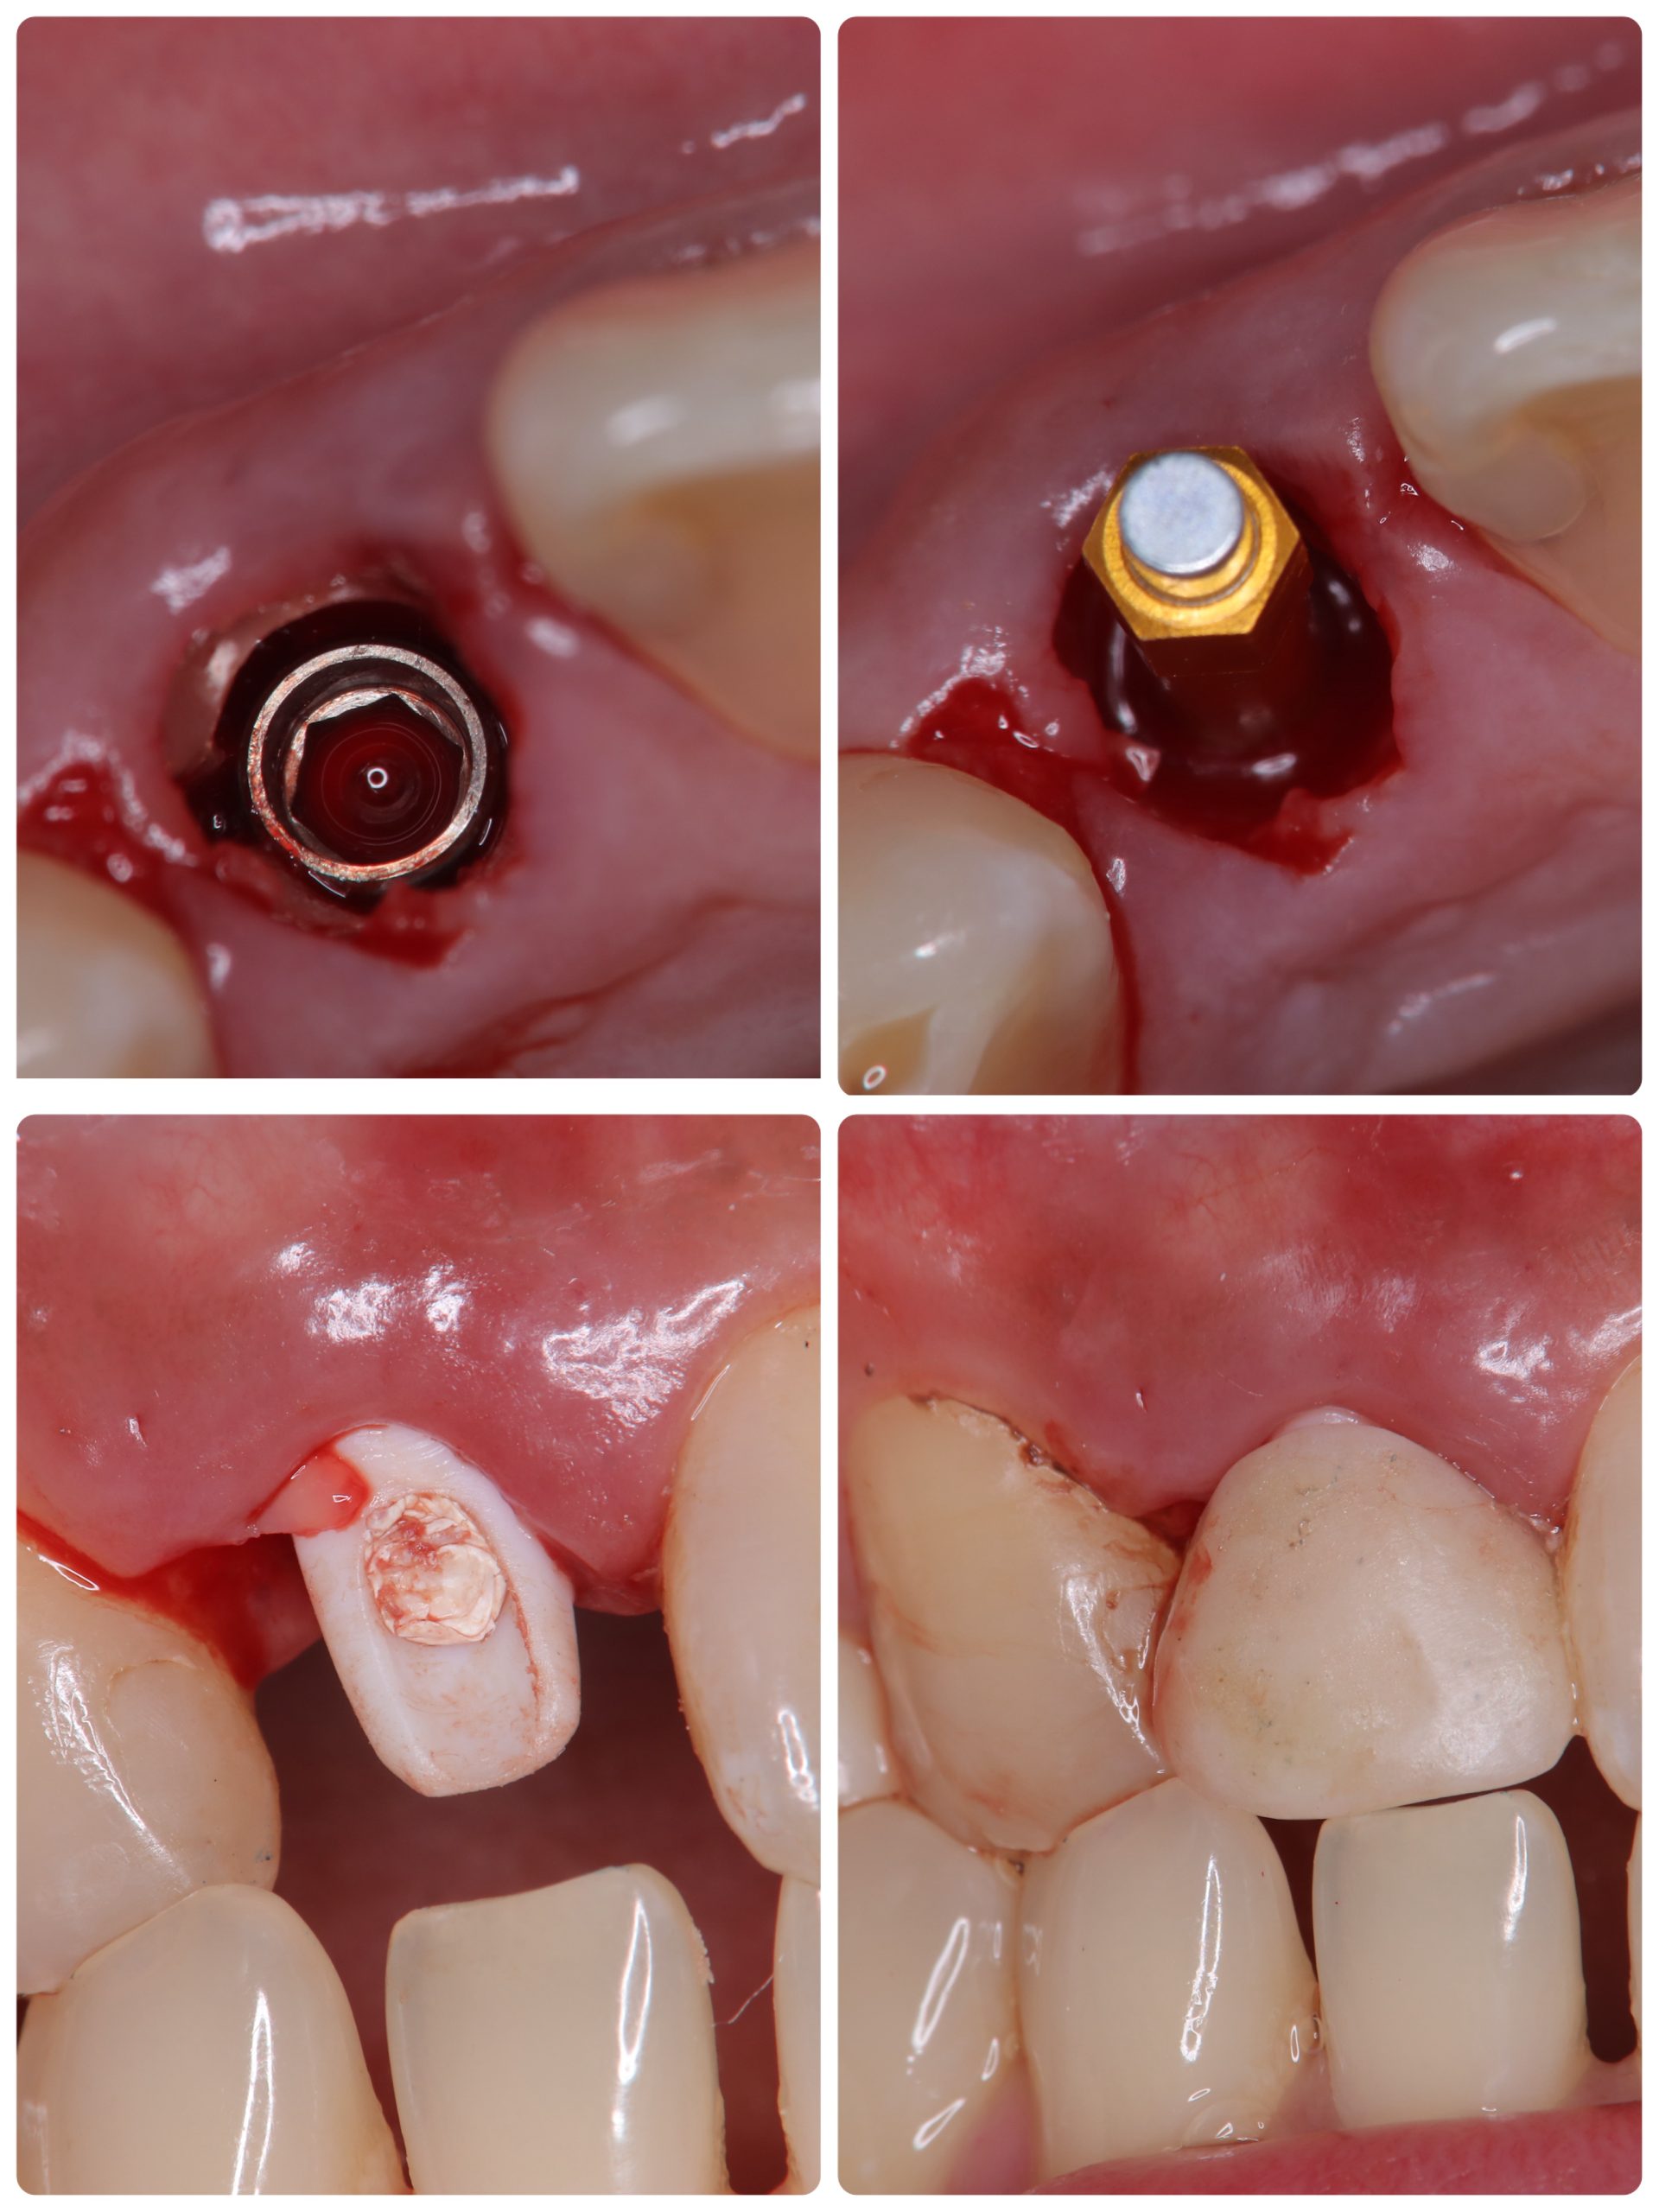

今年5月オペ、6番は残存骨2から3ミリ程度での、ソケットリフトデンサーバーによるリフト

4.5番は6wで仮歯装着、しかし6番は5ヶ月近くかかったが、本日最終補綴物セット

ジンジバルカウンツアー(擬似歯肉)、ペディフィケーションジグインデックス

昼からは前歯抜歯即時、ソケットシールド、即時荷重まで 切開無し